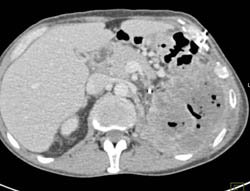

Gastric and Duodenal Lipoma